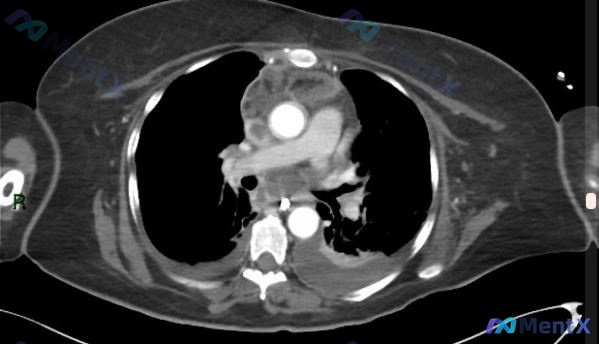

看到这个很有代表性的急重症病例,整理一下资料和分析思路,和大家一起讨论。 病例基本信息 患者基础情况:59岁男性,有10年高血压病史,自行停药多年未随访,20包年吸烟史。 主诉:声音嘶哑进行性加重2周,突发剧烈胸痛2小时不缓解。 现病史与体征 - 声音嘶哑2周前逐渐出现,持续加重;2小时前突发剧烈胸...